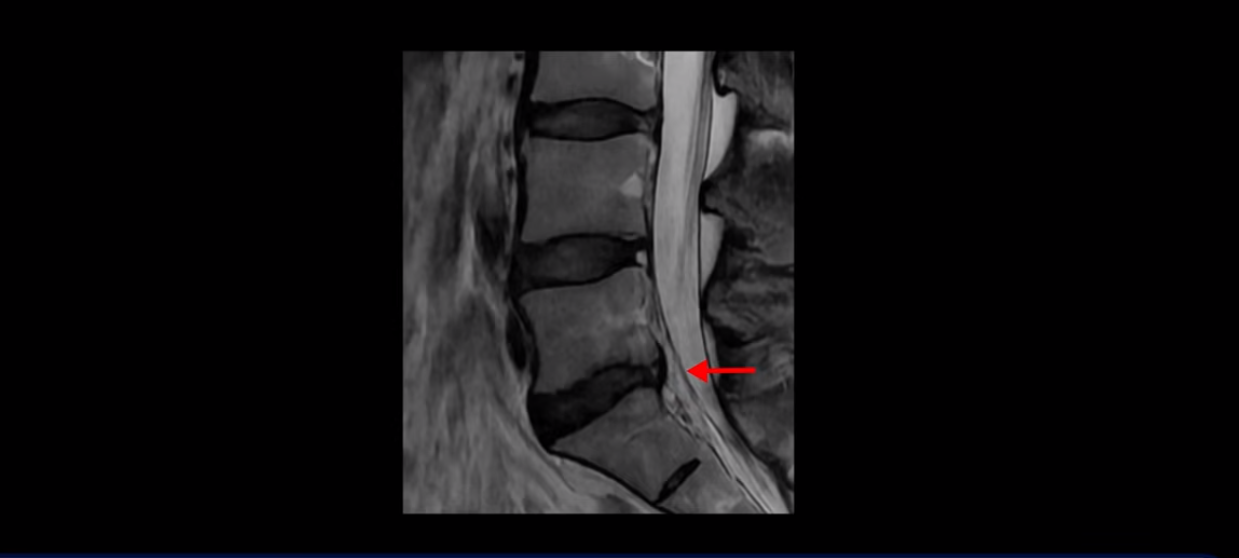

우선 이분 허리 MRI를 보면 5번 1번에 퇴행성 디스크가 있지만 방사통을 일으킬 만큼 신경을 누르고 있어 보이지 않습니다.

오른쪽으로 디스크가 약간 찢어져 보이는데, 작년에 찍은 MRI에서도 보이는 것이라 오래 전에 찢어진 후 아문 흔적으로 보입니다.

중요한 것은 오른쪽 다리에 심한 방사통이 있다든가 재채기를 못 한다거나 허리를 구부리거나 몸을 살짝 비틀 때 날카로운 통증이 없습니다. 즉, 섬유륜이 최근에 찢어진 게 아닌 겁니다.

4번 5번과 3번 4번 마디도 디스크가 중앙으로 살짝 밀려나와있지만 최근에 섬유륜이 찢어진 것도 아니고, 신경 다발을 누를 정도로 심하게 밀려나와 있는 것도 전혀 아닙니다.

양쪽 신경 가지가 빠져나가는 추간공도 충분히 넓어서 신경학적 방사통을 일으킬 여지가 없습니다.